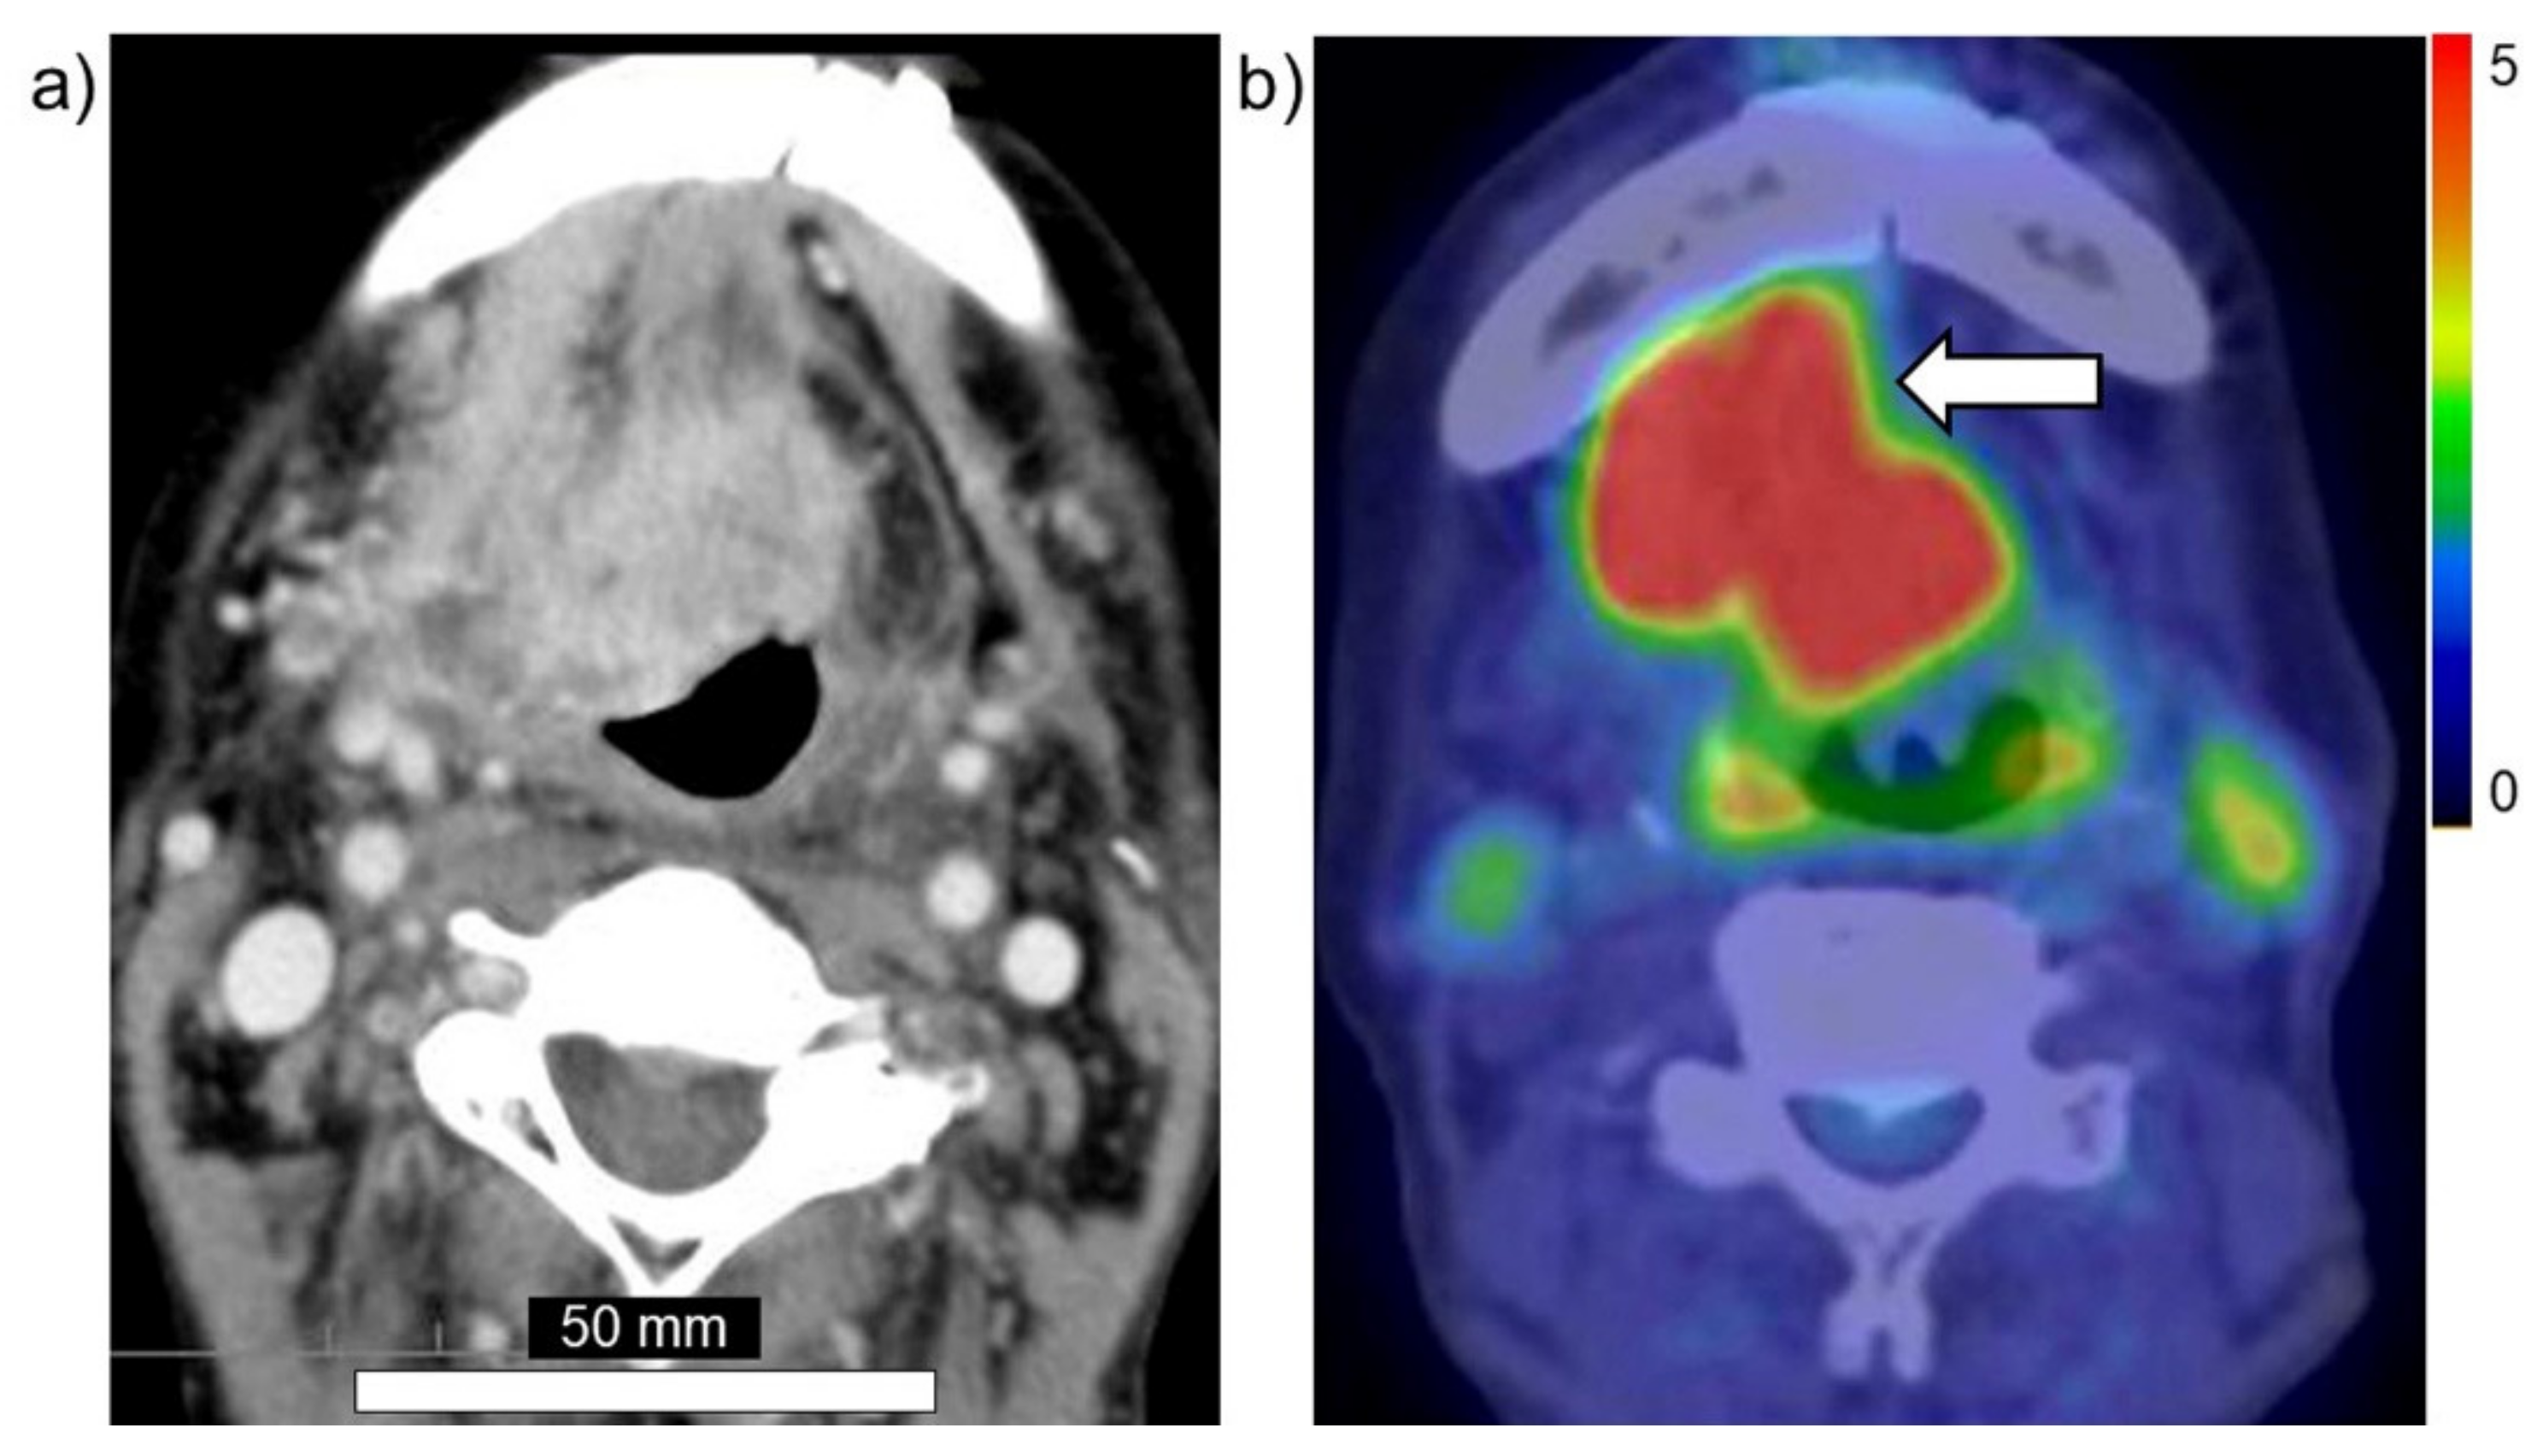

Taken together, these findings suggest that PET using 18FBPA is a useful and reliable treatment strategy for BNCT that is mainly used for determining the treatment indications, predicting the distribution of the 10B in the tumor and surrounding normal tissues, and enabling high-precision treatment planning. Figure 3a,b show brain tumor. Gadolinium enhanced lesion is found in the left parieto-occipital lobe, and abnormal accumulation is also found in 18FBPA PET. Figure 4a,b show tongue cancer. Huge tumor with high 18FBPA accumulation is seen in the floor of the right oral cavity and reaches the mandible. Figure 5a,b show melanoma. Abnormal accumulation is seen in the right neck.

Figure 4. Head and neck cancer (tongue cancer). (a) MRI, (b) 18FBPA PET. Arrow presents tumor lesion. Accumulation is shown in rainbow-color scale (high in red and low in blue).